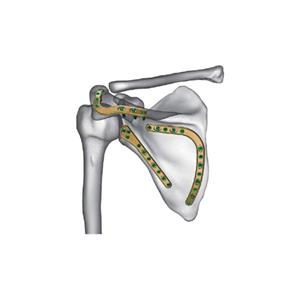

لوحة العظام الجراحية لزرع سبائك التيتانيوم في جسم الإنسان

غالبًا ما تستخدم صفائح العظام الجراحية المزروعة من سبائك التيتانيوم لعلاج كسور العظام أو التشوهات في جسم الإنسان. التيتانيوم معدن قوي وخفيف الوزن متوافق حيوياً ، مما يعني أنه لا يسبب أي ردود فعل سلبية أو رفض من قبل الجهاز المناعي للجسم.